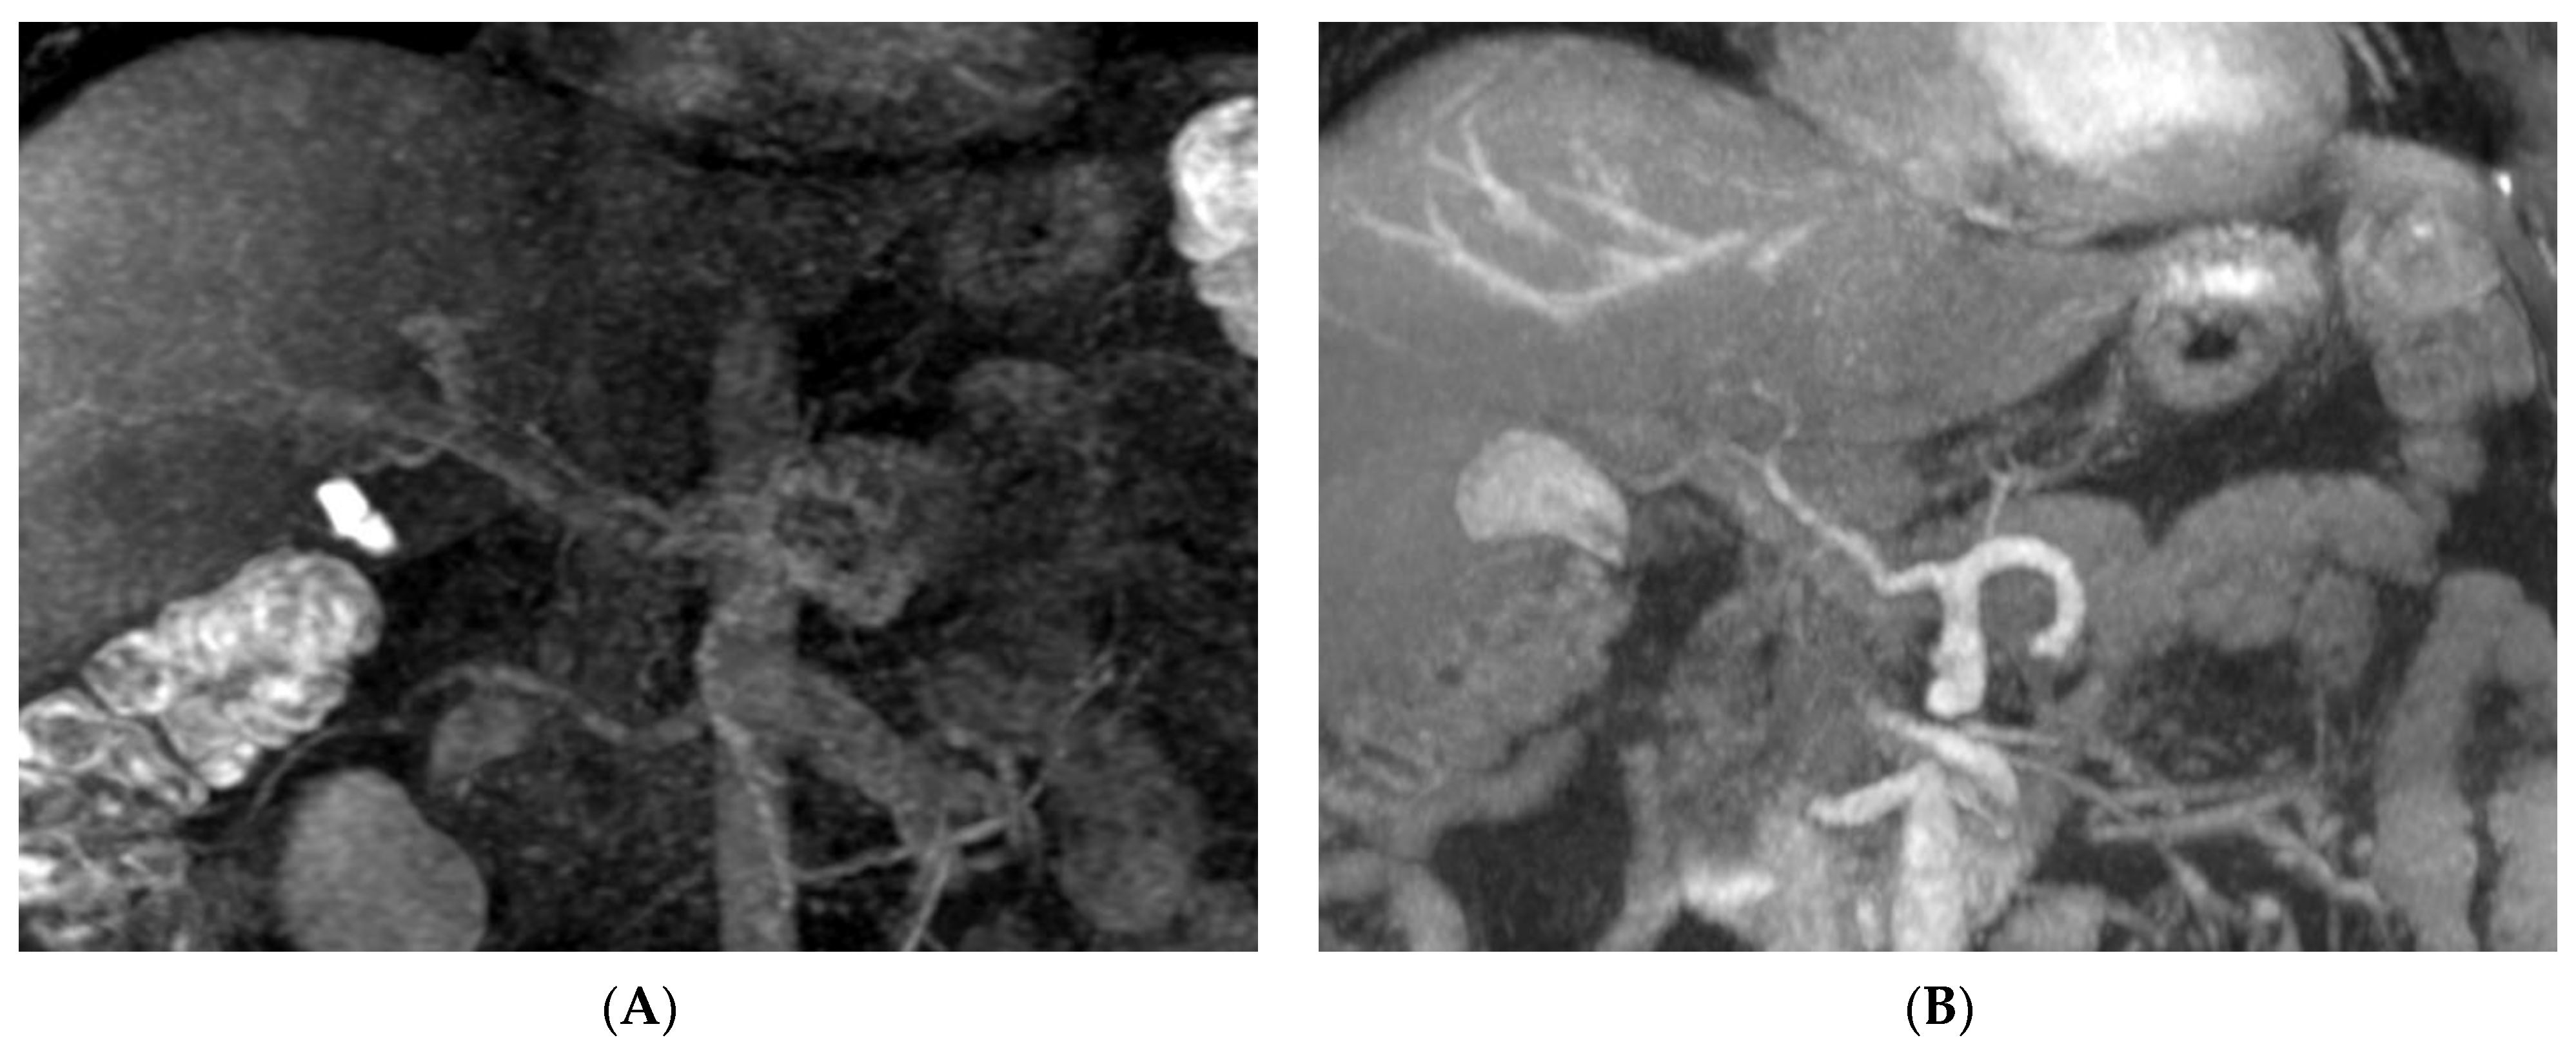

Results of the present study show that the pretransplant vascular anatomy can be well identified using combined non-CE MRA and CMRA of the hepatic arteries (100%), PVs (98%), and hepatic vein (100%), and results compare favorably with CTA and correlate well with the intraoperative findings in all donors, achieving a 100% diagnostic accuracy rate for pretransplant vascular anatomy. The main feature of IFIR in non-CE MRA is the placement of the selective inversion pulse to saturate the background signal, which then selectively acquires the vessel of interest inflow information [15]. Selectively visualizing the specific vascular structure has the advantage of decreasing the overlapping of unwanted vessels, which allows us to assess the vascular pattern more clearly (Figure 2). Magnetic resonance cholangiopancreatography (MRCP) includes mandatory steps for the evaluation of potential donors in LDLT. Combined non-CE MRA and CMRA demonstrate comparable diagnostic ability with CTA and provides enhanced biliary anatomical information that optimizes donor safety.

Figure 2.

Selective visualization of hepatic vasculature in non-CE MRA compared with CMRA: (A) Selective depiction of hepatic artery of a 24-year-old female donor. Partial hepatic vein signal in the superior part of the liver due to non-saturated region, but without obscuring hepatic artery. (B) Clear depiction of hepatic veins of a 32-year-old male donor without portal vein overlapping; high signal of gallbladder was also depicted but does not interfere with the interpretation of hepatic veins. (C) A 24-year-old female donor’s portal veins are also clearly depicted. (D) CMRA of hepatic veins in the same donor as in (C), with portal vein overlapping and one IRHV (white arrow) crossing over the right portal vein.

When vessels were quantified by acquiring vascular signal intensity and calculating the CNR, the average CNR of the portal vein and hepatic vein in non-CE MRA was significantly higher than that in CMRA, in which the portal venous phase and hepatic venous phase need imaging time delay, while contrast medium flows into both the liver parenchyma and vessel, decreasing the contrast of the vessel compared with the surrounding liver parenchyma. This accounts for the high identification rate of the portal venous system and hepatic venous system in non-CE MRA. No significant differences were shown in the CNR of hepatic arteries between non-CE MRA and CMRA, but the CNR of distal artery branches in non-CE MRA was less than that in CMRA. To identify the anatomic type of the hepatic artery, non-CE MRA has optimal diagnostic ability of the proximal segment of the hepatic artery, which provides sufficient information about hepatic artery type. However, CMRA has better diagnostic ability in identifying S4HA than non-CE MRA. In the present study, the hepatic artery images of two donors had poor-quality CMRA images due to scan delay time errors after contrast medium injection; however, the hepatic artery images had optimal quality in non-CE MRA for identifying the hepatic artery pattern. Since the beneficial characteristic of non-CE MRA is its freedom from contrast medium injection, it can be performed repeatedly. If a donor has suboptimal imaging quality in CTA and CMRA images for diagnosis, non-CE MRA is the ideal alternative of acquiring vascular images without contrast medium administration and repeating the studies until the satisfying image is obtained (Figure 3).

Non-CE MRA is an alternative way of acquiring vascular image. A 45-year-old male donor candidate has suboptimal hepatic artery image in CMRA (A). The non-CE MRA (B) provides diagnosable delineation of hepatic artery pattern.